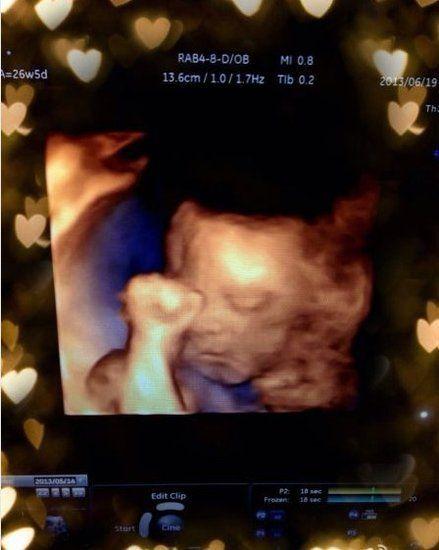

(图片来源网络,侵删)- 对于月经不规律或备孕时间较长的女性,医生通常会建议进行排卵监测B超。

- 从月经周期的第8-10天开始,每隔1-2天做一次B超,动态监测卵泡的发育、成熟和排出情况。

- 这样可以精准地找到排卵日,指导夫妻在最佳的“受孕窗口期”同房,大大提高怀孕几率。